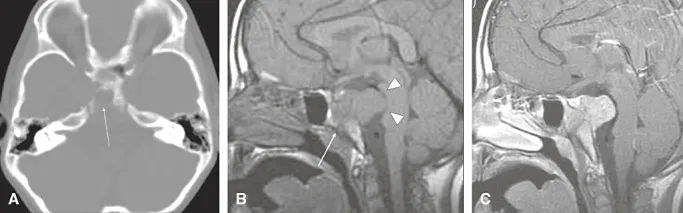

神经影像学检查显示斜坡区骨质破坏性病变,病灶位于蝶鞍平面以下,伴有巨大软组织成分向颅内扩展。影像学特征包括:病灶呈实性、分叶状,信号均匀,明显强化,T2低信号提示细胞密度高。

平扫CT检查显示斜坡广泛骨质破坏,病灶位于斜坡中心区域,无骨性或软骨样基质。MRI平扫T1加权像呈等信号,T2加权像呈低信号表现。增强扫描后病灶呈现均匀强化。MRI进一步显示分叶状实性肿块取代蝶枕软骨结合周围斜坡脂肪骨髓的正常高信号,向背侧扩展至桥前池,压迫脑桥并侵犯右侧海绵窦,部分包绕颈内动脉。